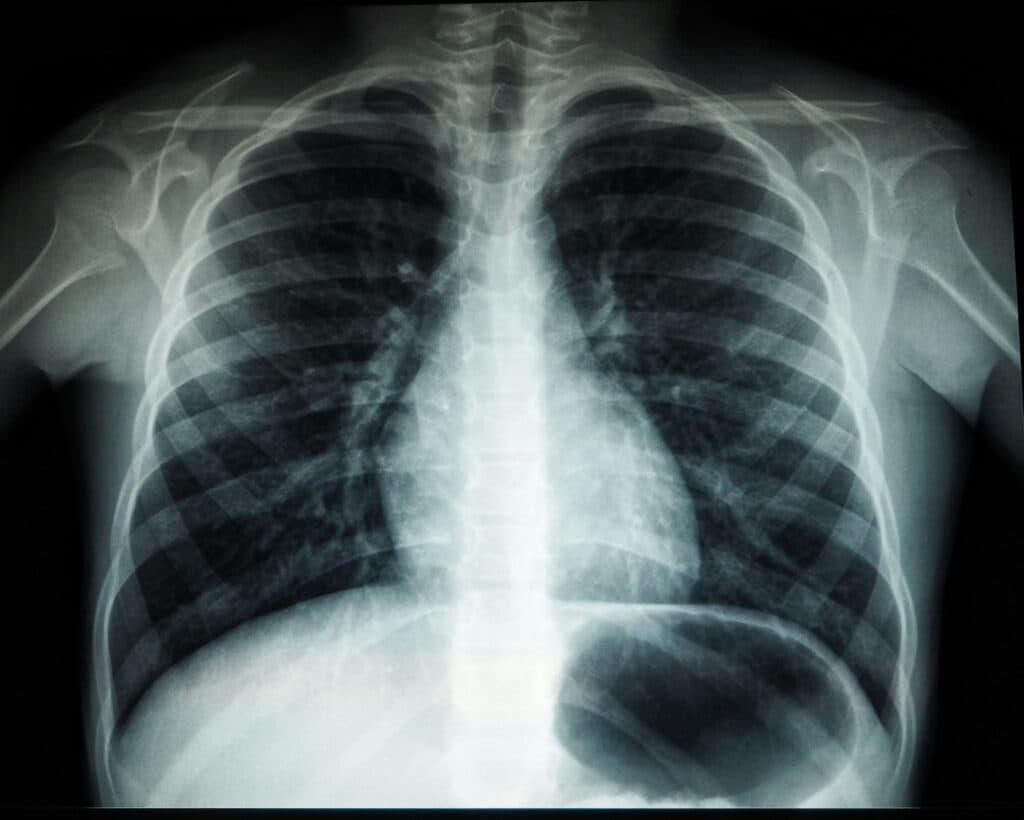

O terceiro episódio disciplinar é particularmente sensível porque se tratou de uma emergência médica. A 31 de Março de 2023, Pedro Cavaco Henriques tentou colocar dois cateteres torácicos num doente com pneumotórax — situação em que o ar invade a cavidade torácica e provoca o colapso de um pulmão.

As duas tentativas falharam e o doente entrou em insuficiência respiratória, tendo de ser rapidamente transferido para o serviço de urgência, onde acabou estabilizado com drenagem torácica. A médica presente confirmou então a sequência de acontecimentos – e os erros de Pedro Cavaco Henriques – e a perícia médica apontou falha técnica do cirurgião, ainda que reconhecendo que o ambulatório tinha então falta de equipamentos, facto que terá dificultado o procedimento.

A defesa de Pedro Henriques ainda sustentou que não houve violação das leges artis e que a decisão de não insistir após as tentativas falhadas foi prudente, mas o perito da IGAS sublinhou que deveria ter sido pedido um raio-X logo após a primeira tentativa para confirmar a evolução da situação — algo que não foi feito. Também aqui a nota de culpa foi considerada procedente, ainda que com atenuação, dado que a carência de meios foi considerada um factor contribuinte.